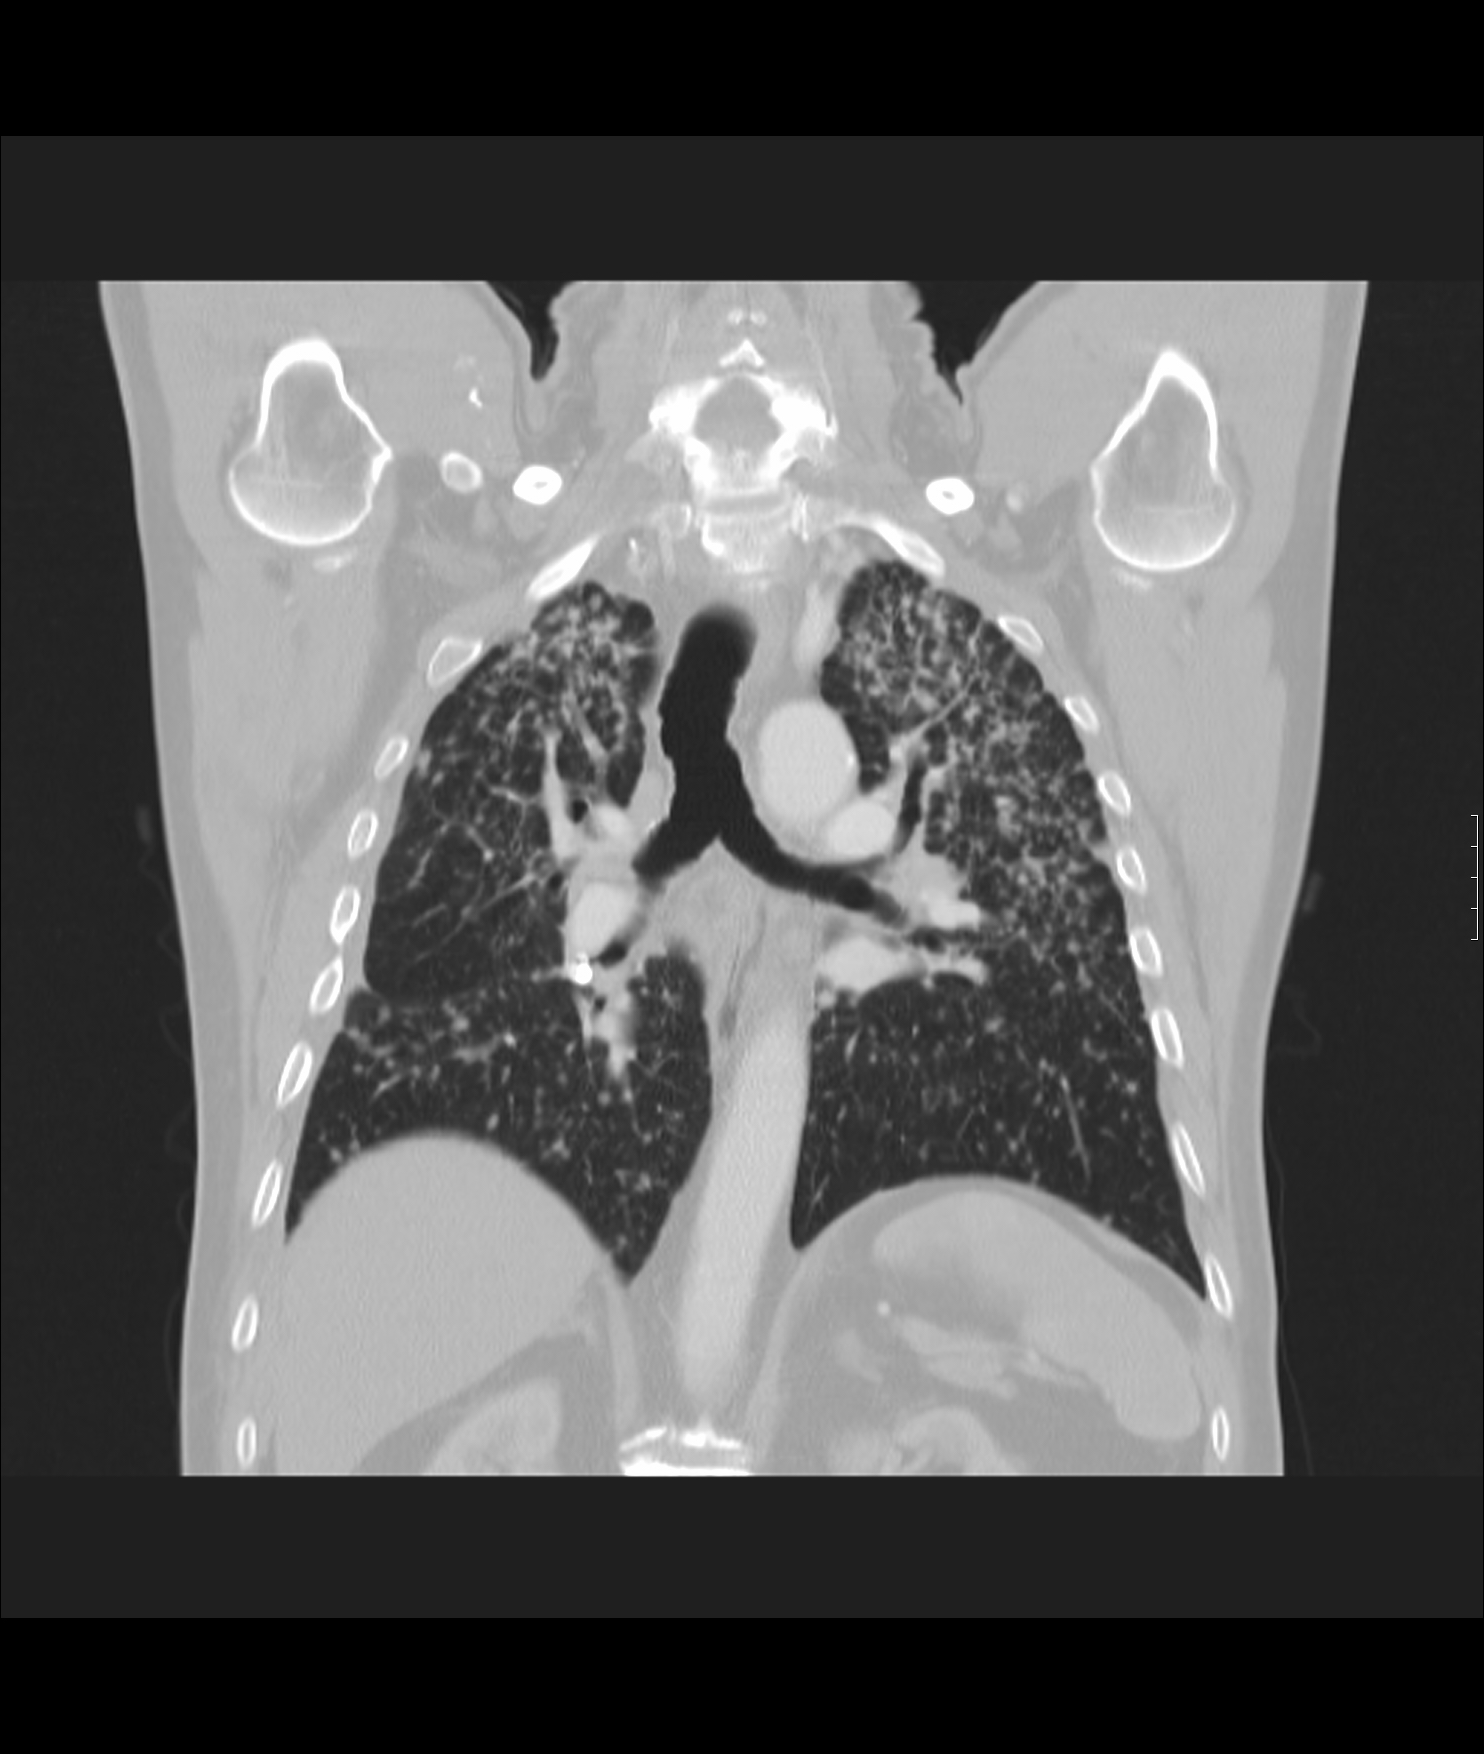

26. ARDS, CT, coronary reconstruction

52 year old woman, dyspnea, septic shock.

Bilateral opacity according to rough, diffuse interstitial edema, irregular atelectasis and bronchogram in the basal segments